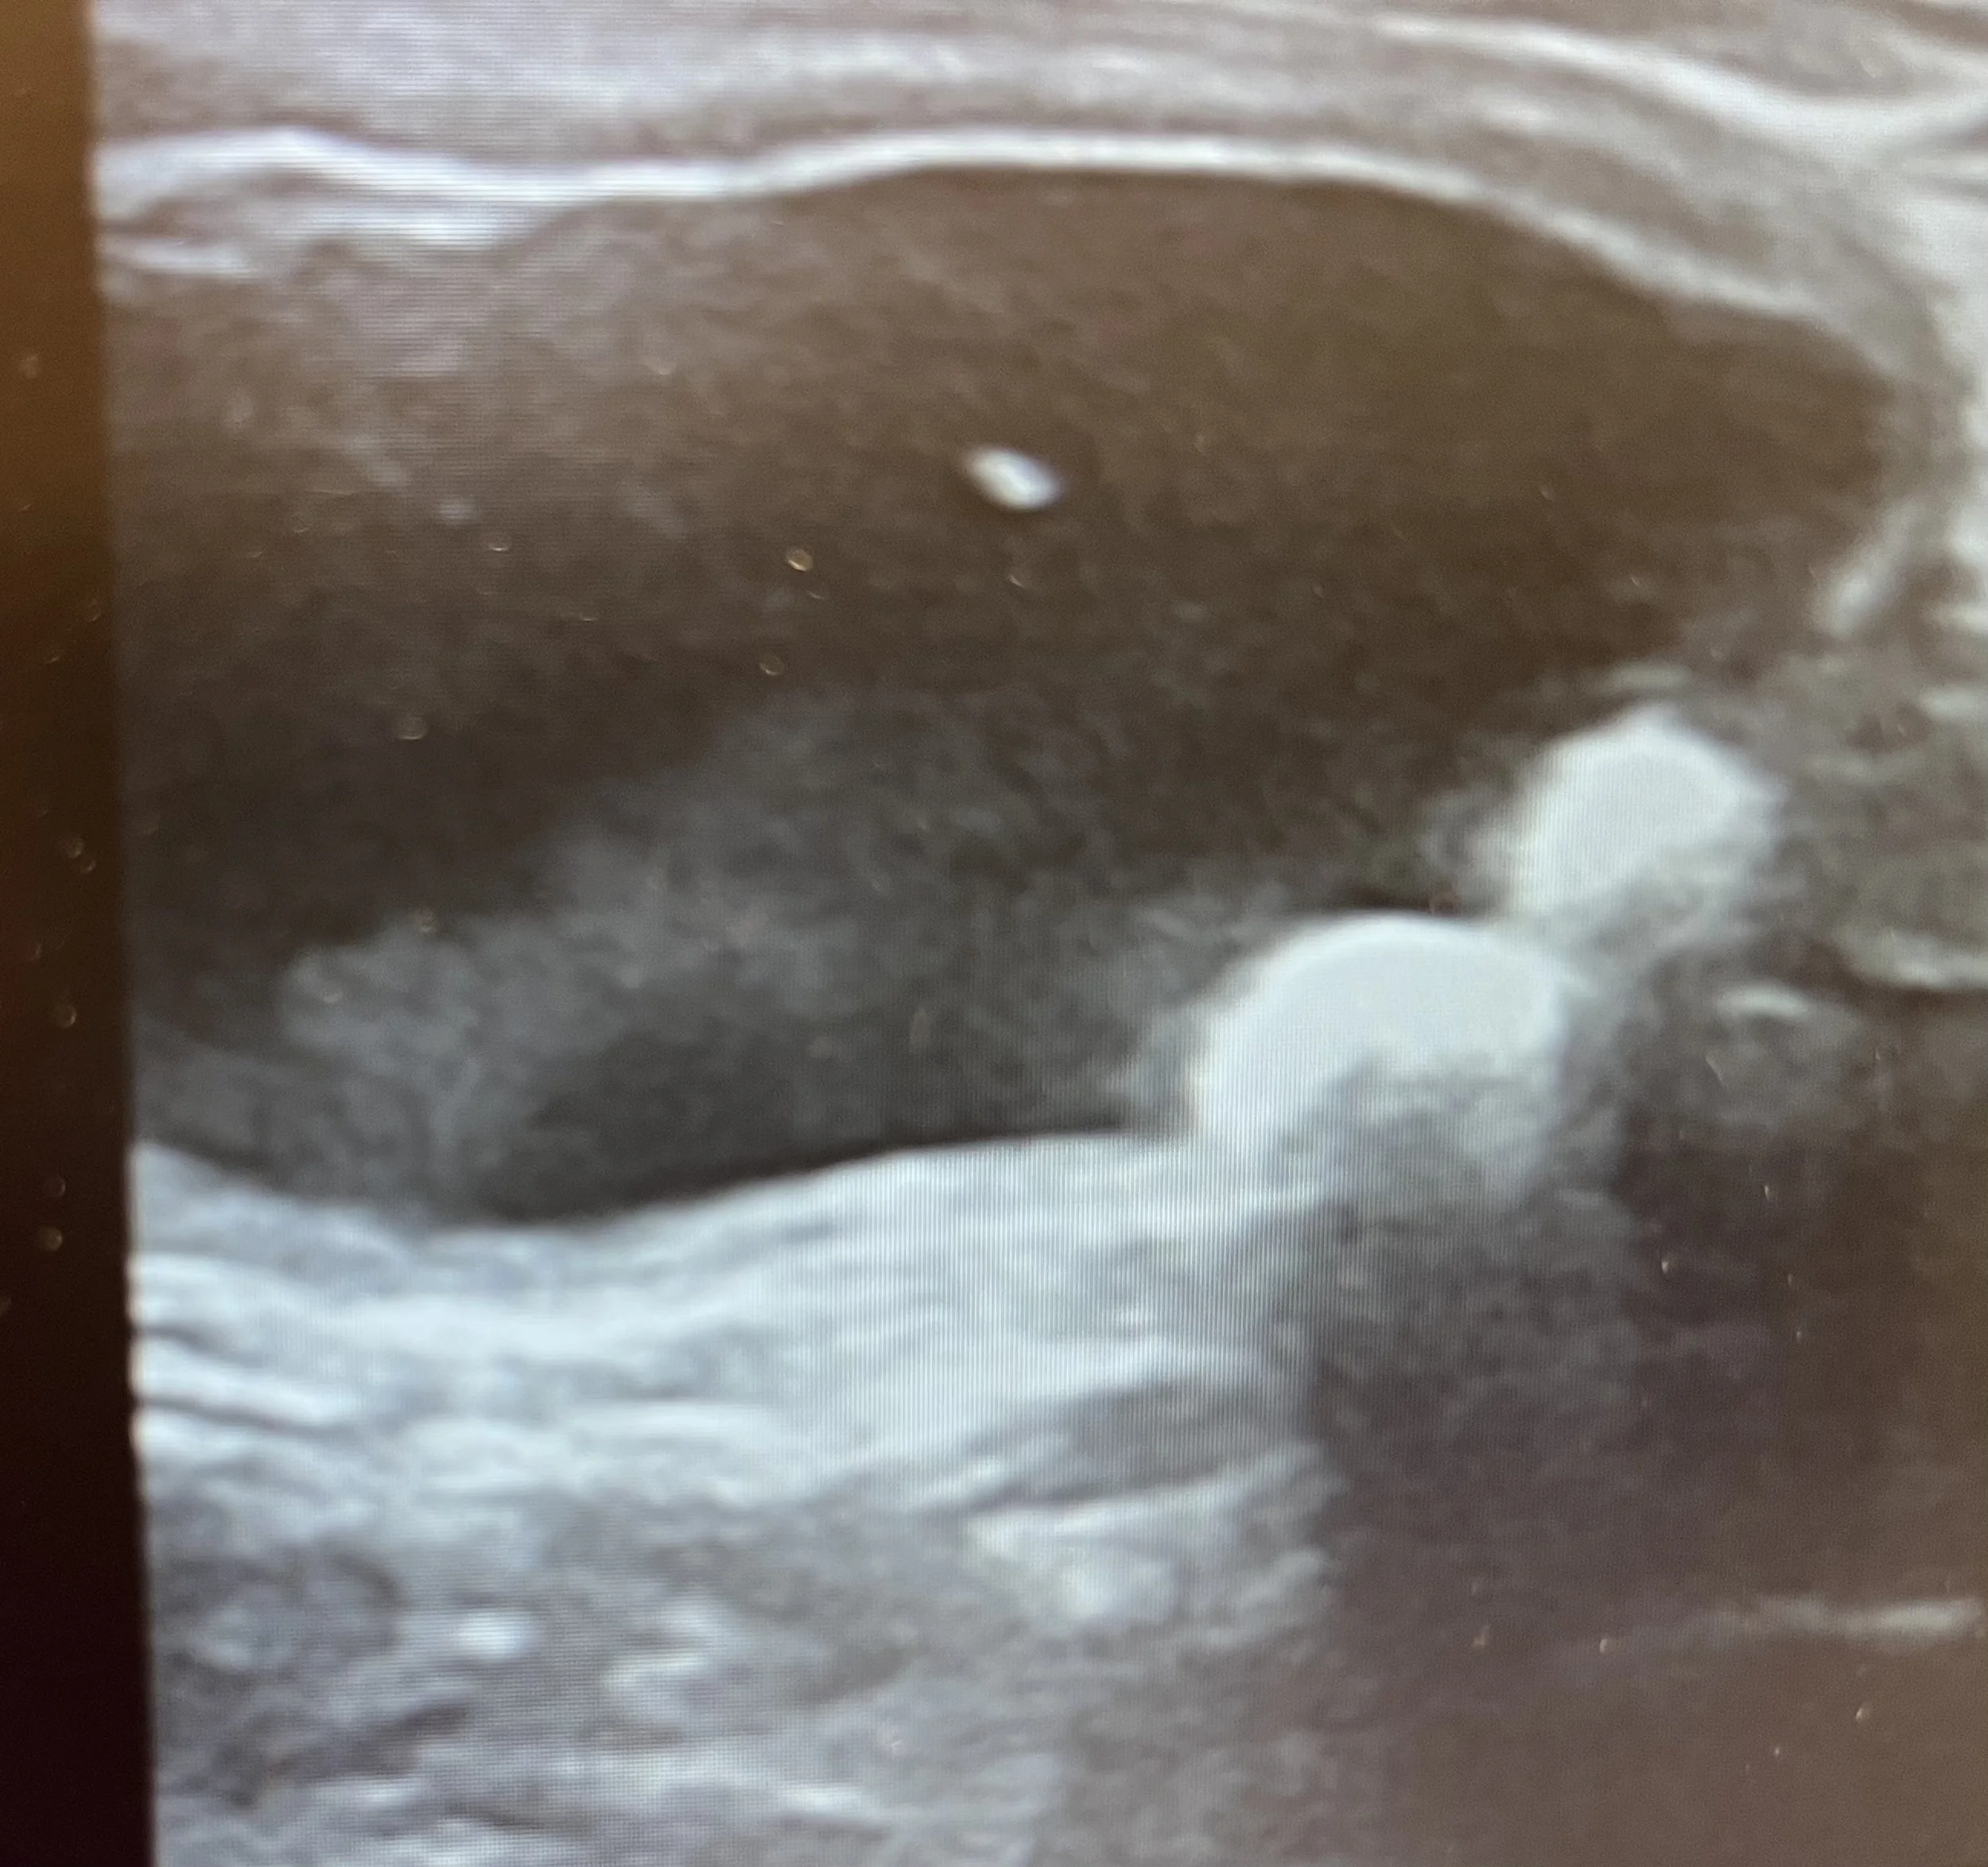

Bilden visar urinsten i urinblåsan hos en katt

• Ultraljud – för att se urinblåsa och urinvägar mer detaljerat, utesluta urinsten läs mer om ultraljudutreding på vår klinik